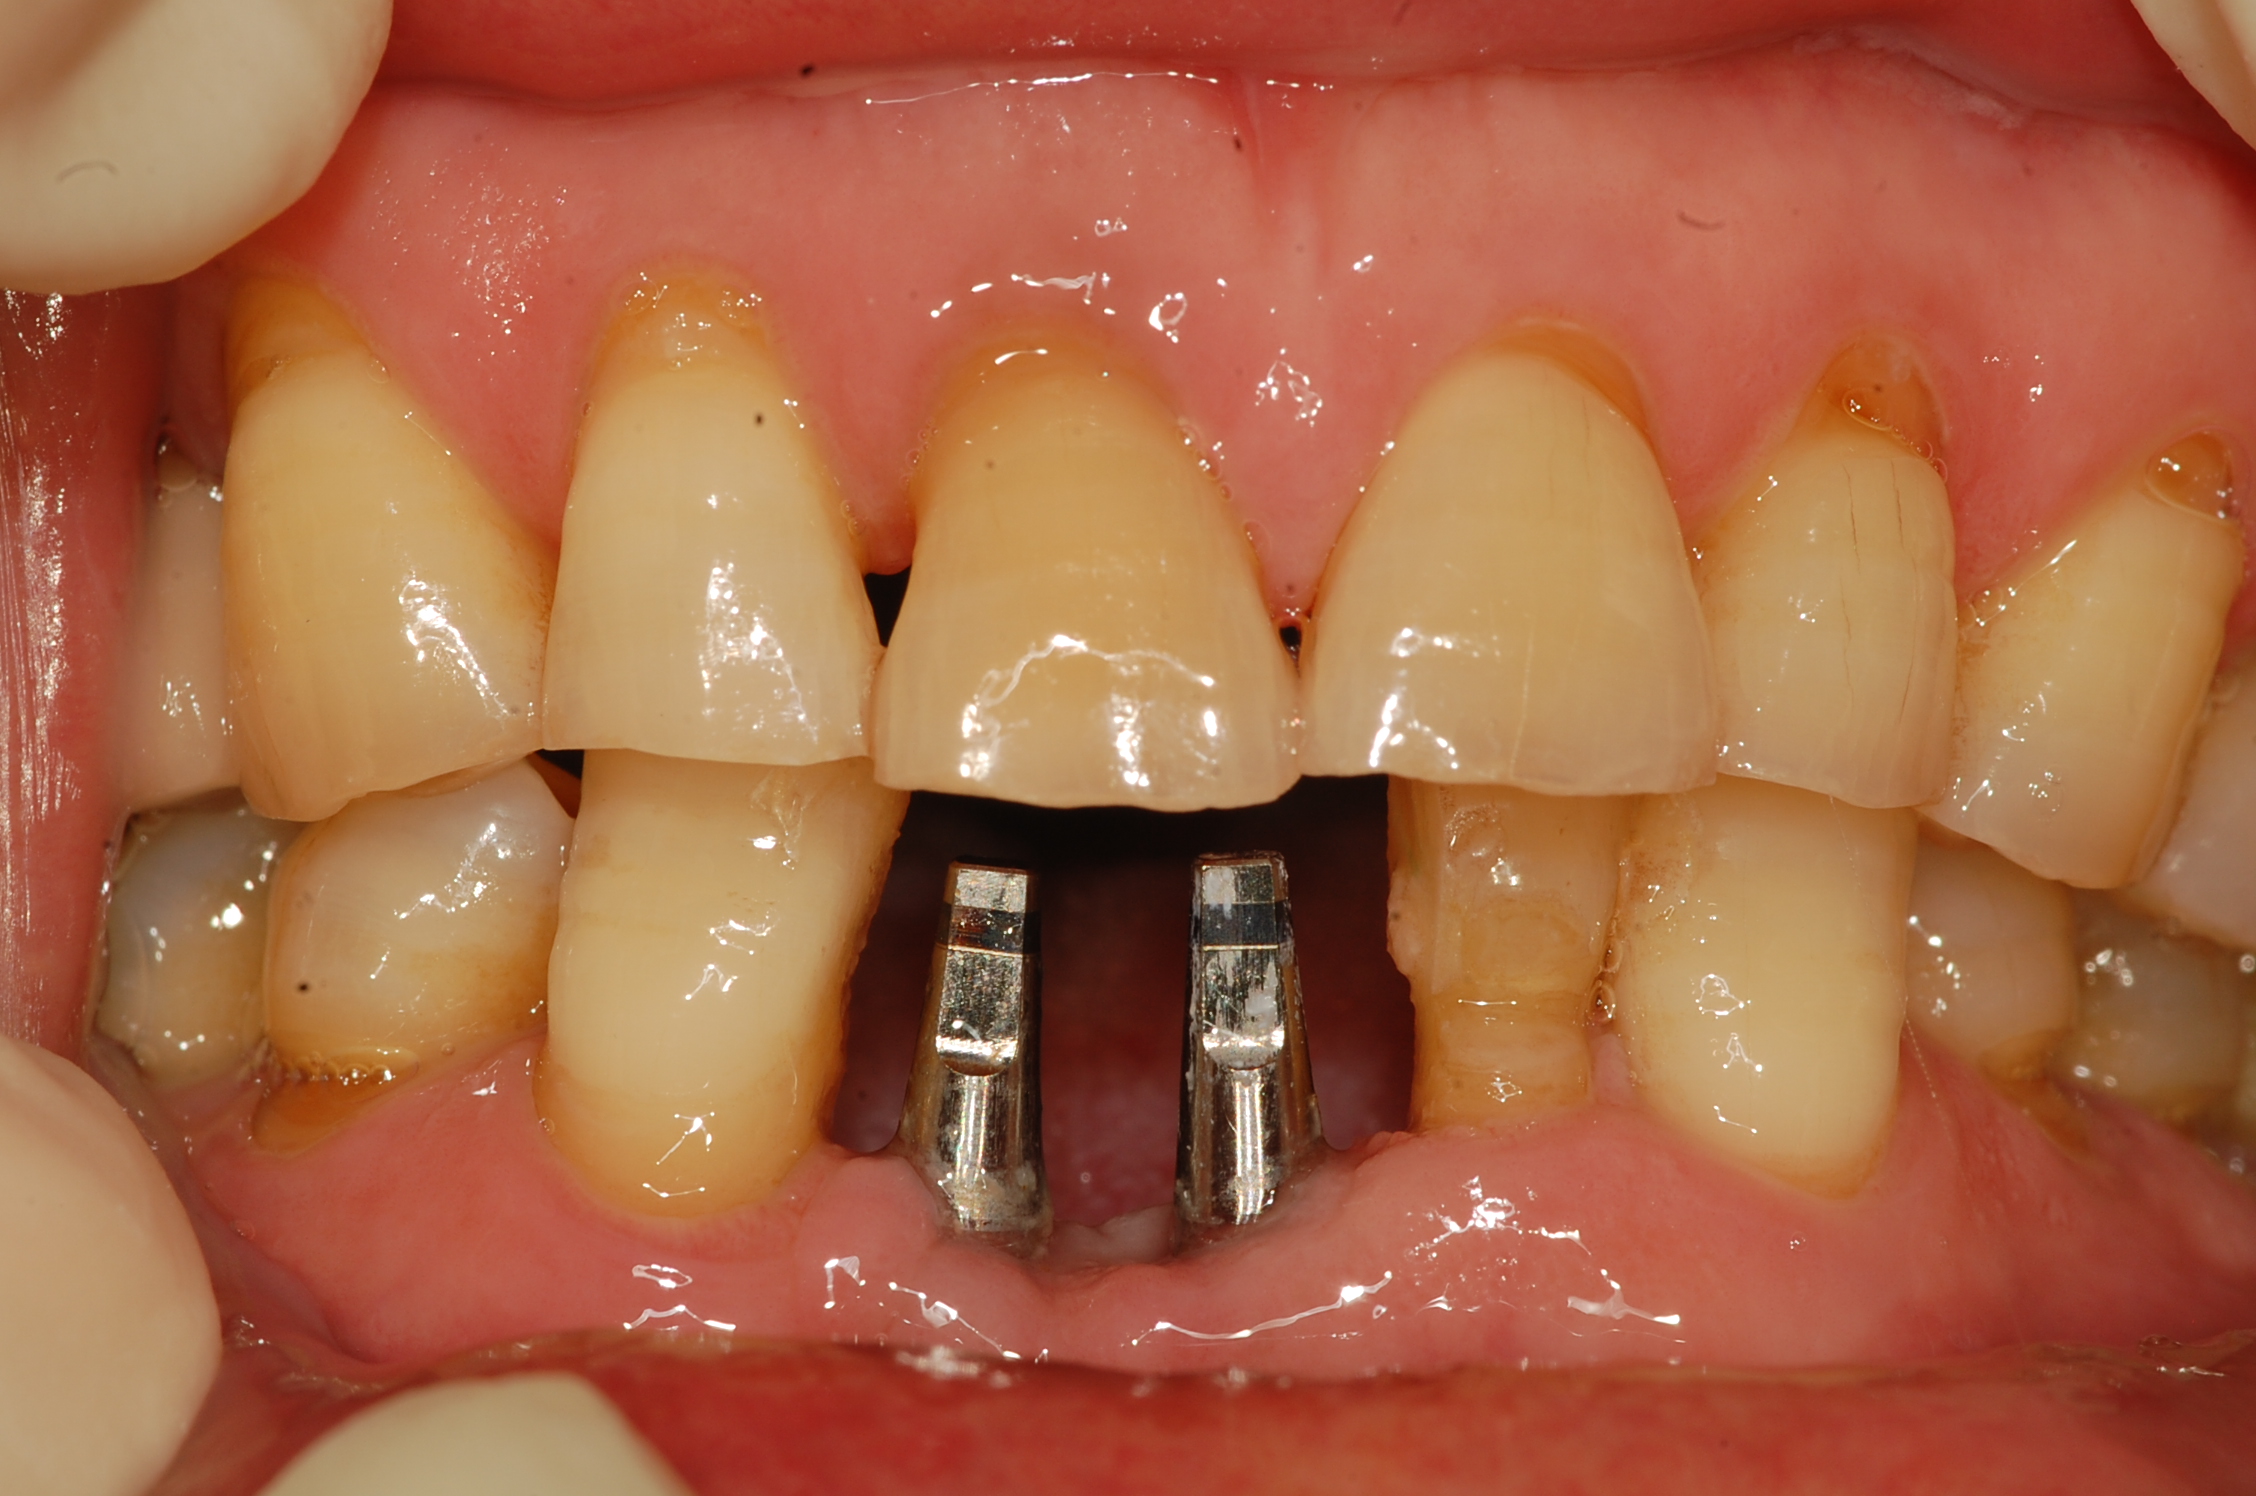

[임플란트] 제목 : 하악 전치부 골폭이 좁은 경우

일체형 임플란트로 . .